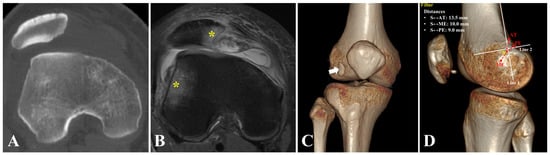

2.5. Positioning of Femoral Tunnel